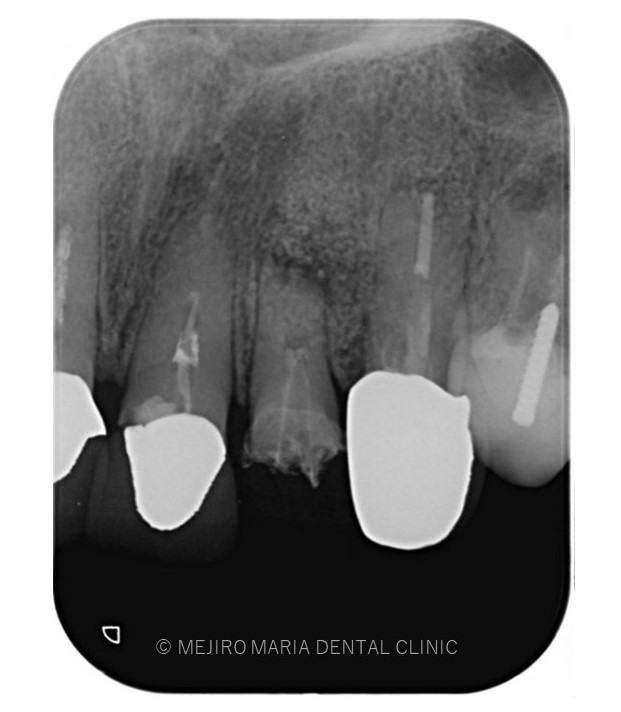

でのリカバリー_術後3ヶ月後のレントゲン画像.jpg)

レントゲン写真より根尖部の骨は3ヶ月で順調に再生していると考えられます。

また、術前に訴えておられた違和感や腫脹、瘻孔は消失しており、現時点で経過は良好であると判断しています。

引き続き経過観察を継続していきます。